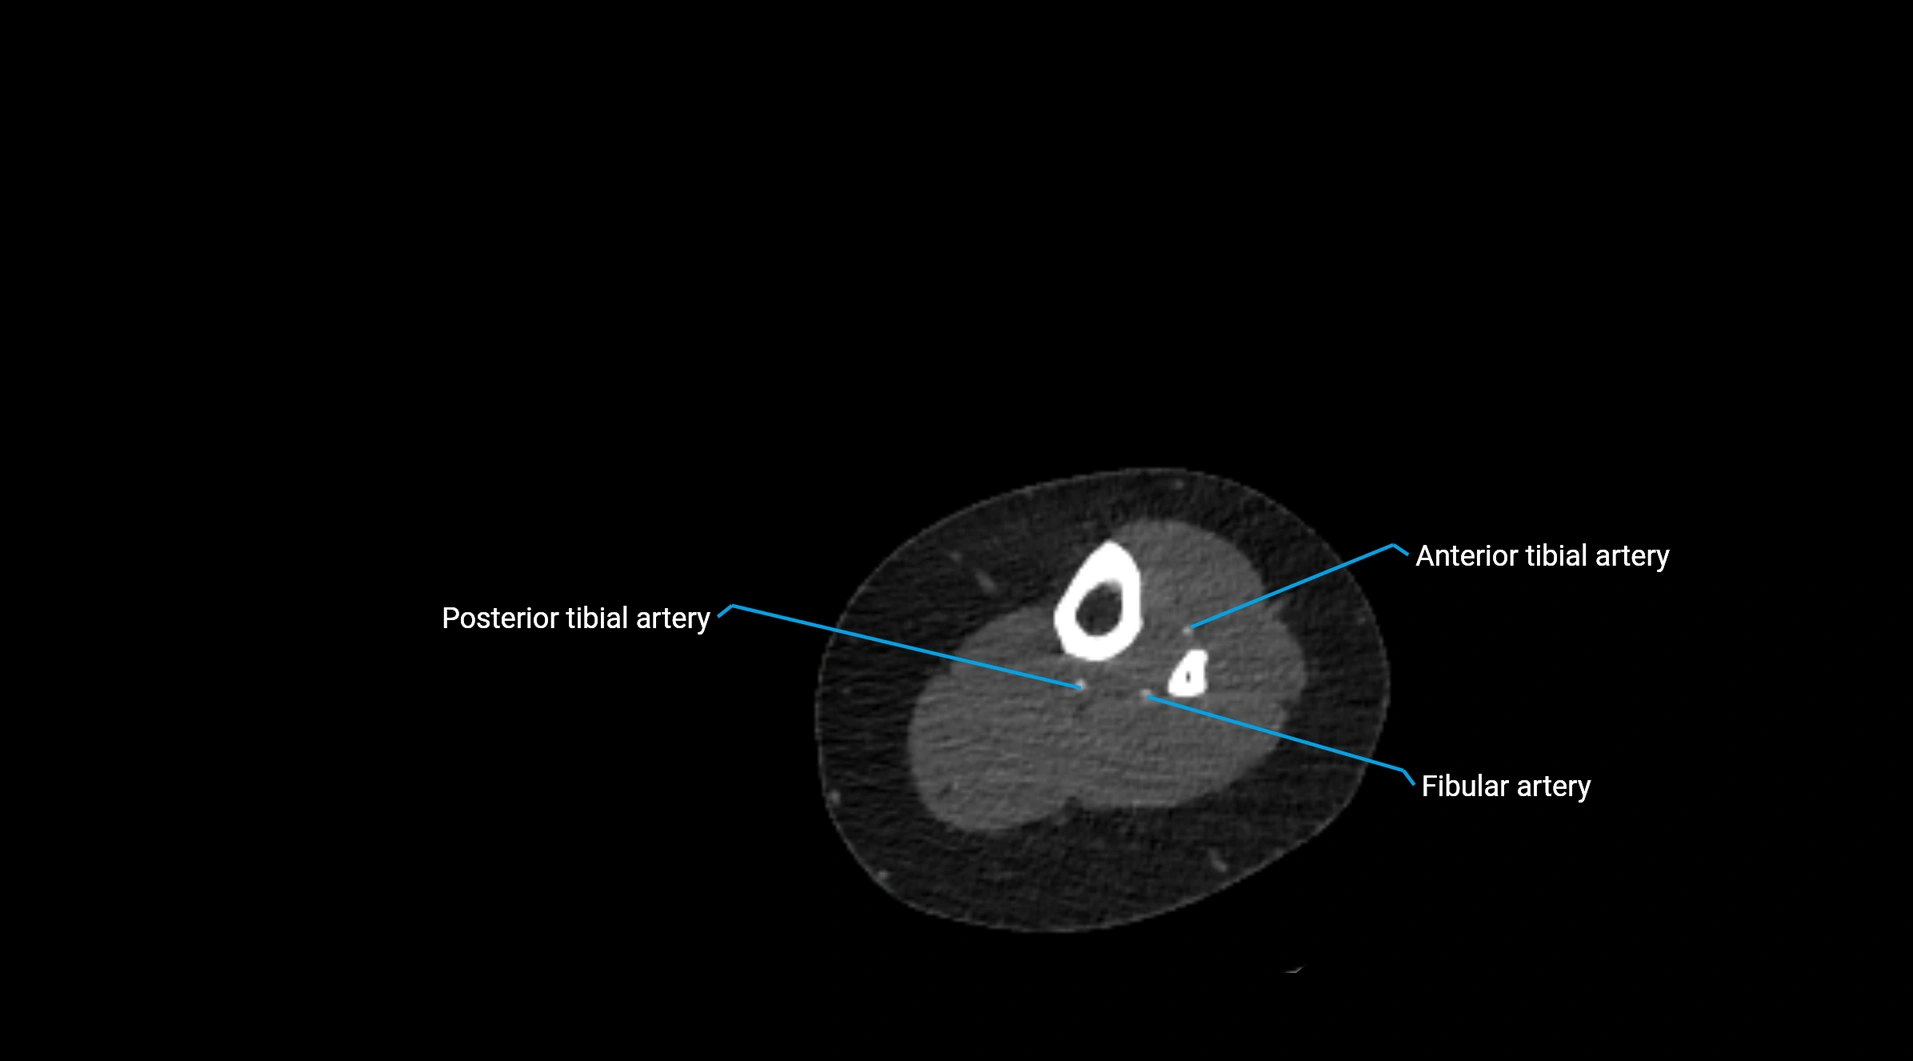

CT images

image